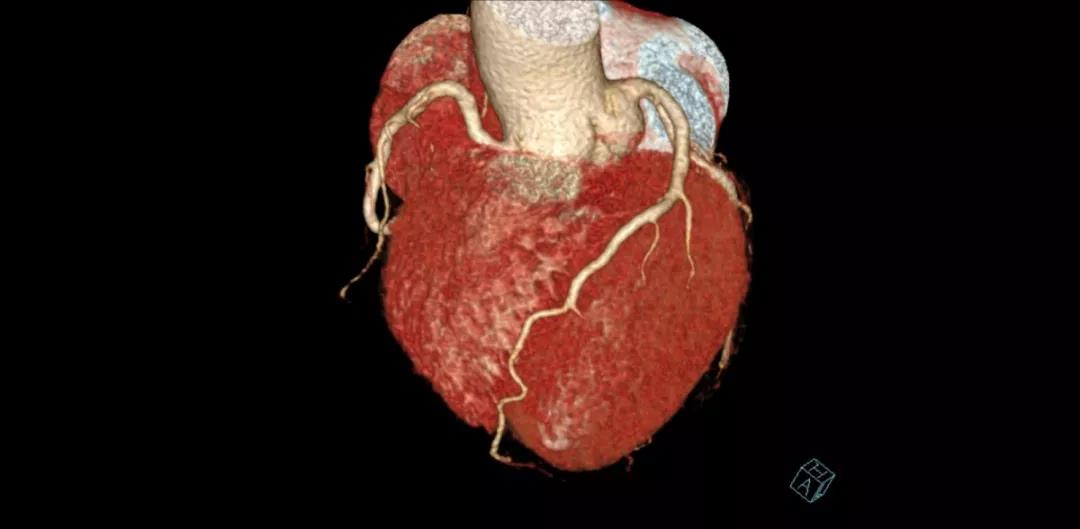

案例圖

冠狀動(dòng)脈CTA